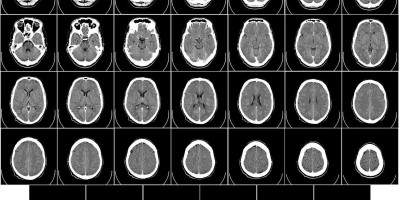

Magnetna rezonanca njenog mozga otkrila je abnormalnosti koje zahtevaju operaciju. Lekari su utvrdili da se radi o vrsti Ophidascaris robertsi, a crveni parazit je mogao biti tamo do dva meseca.